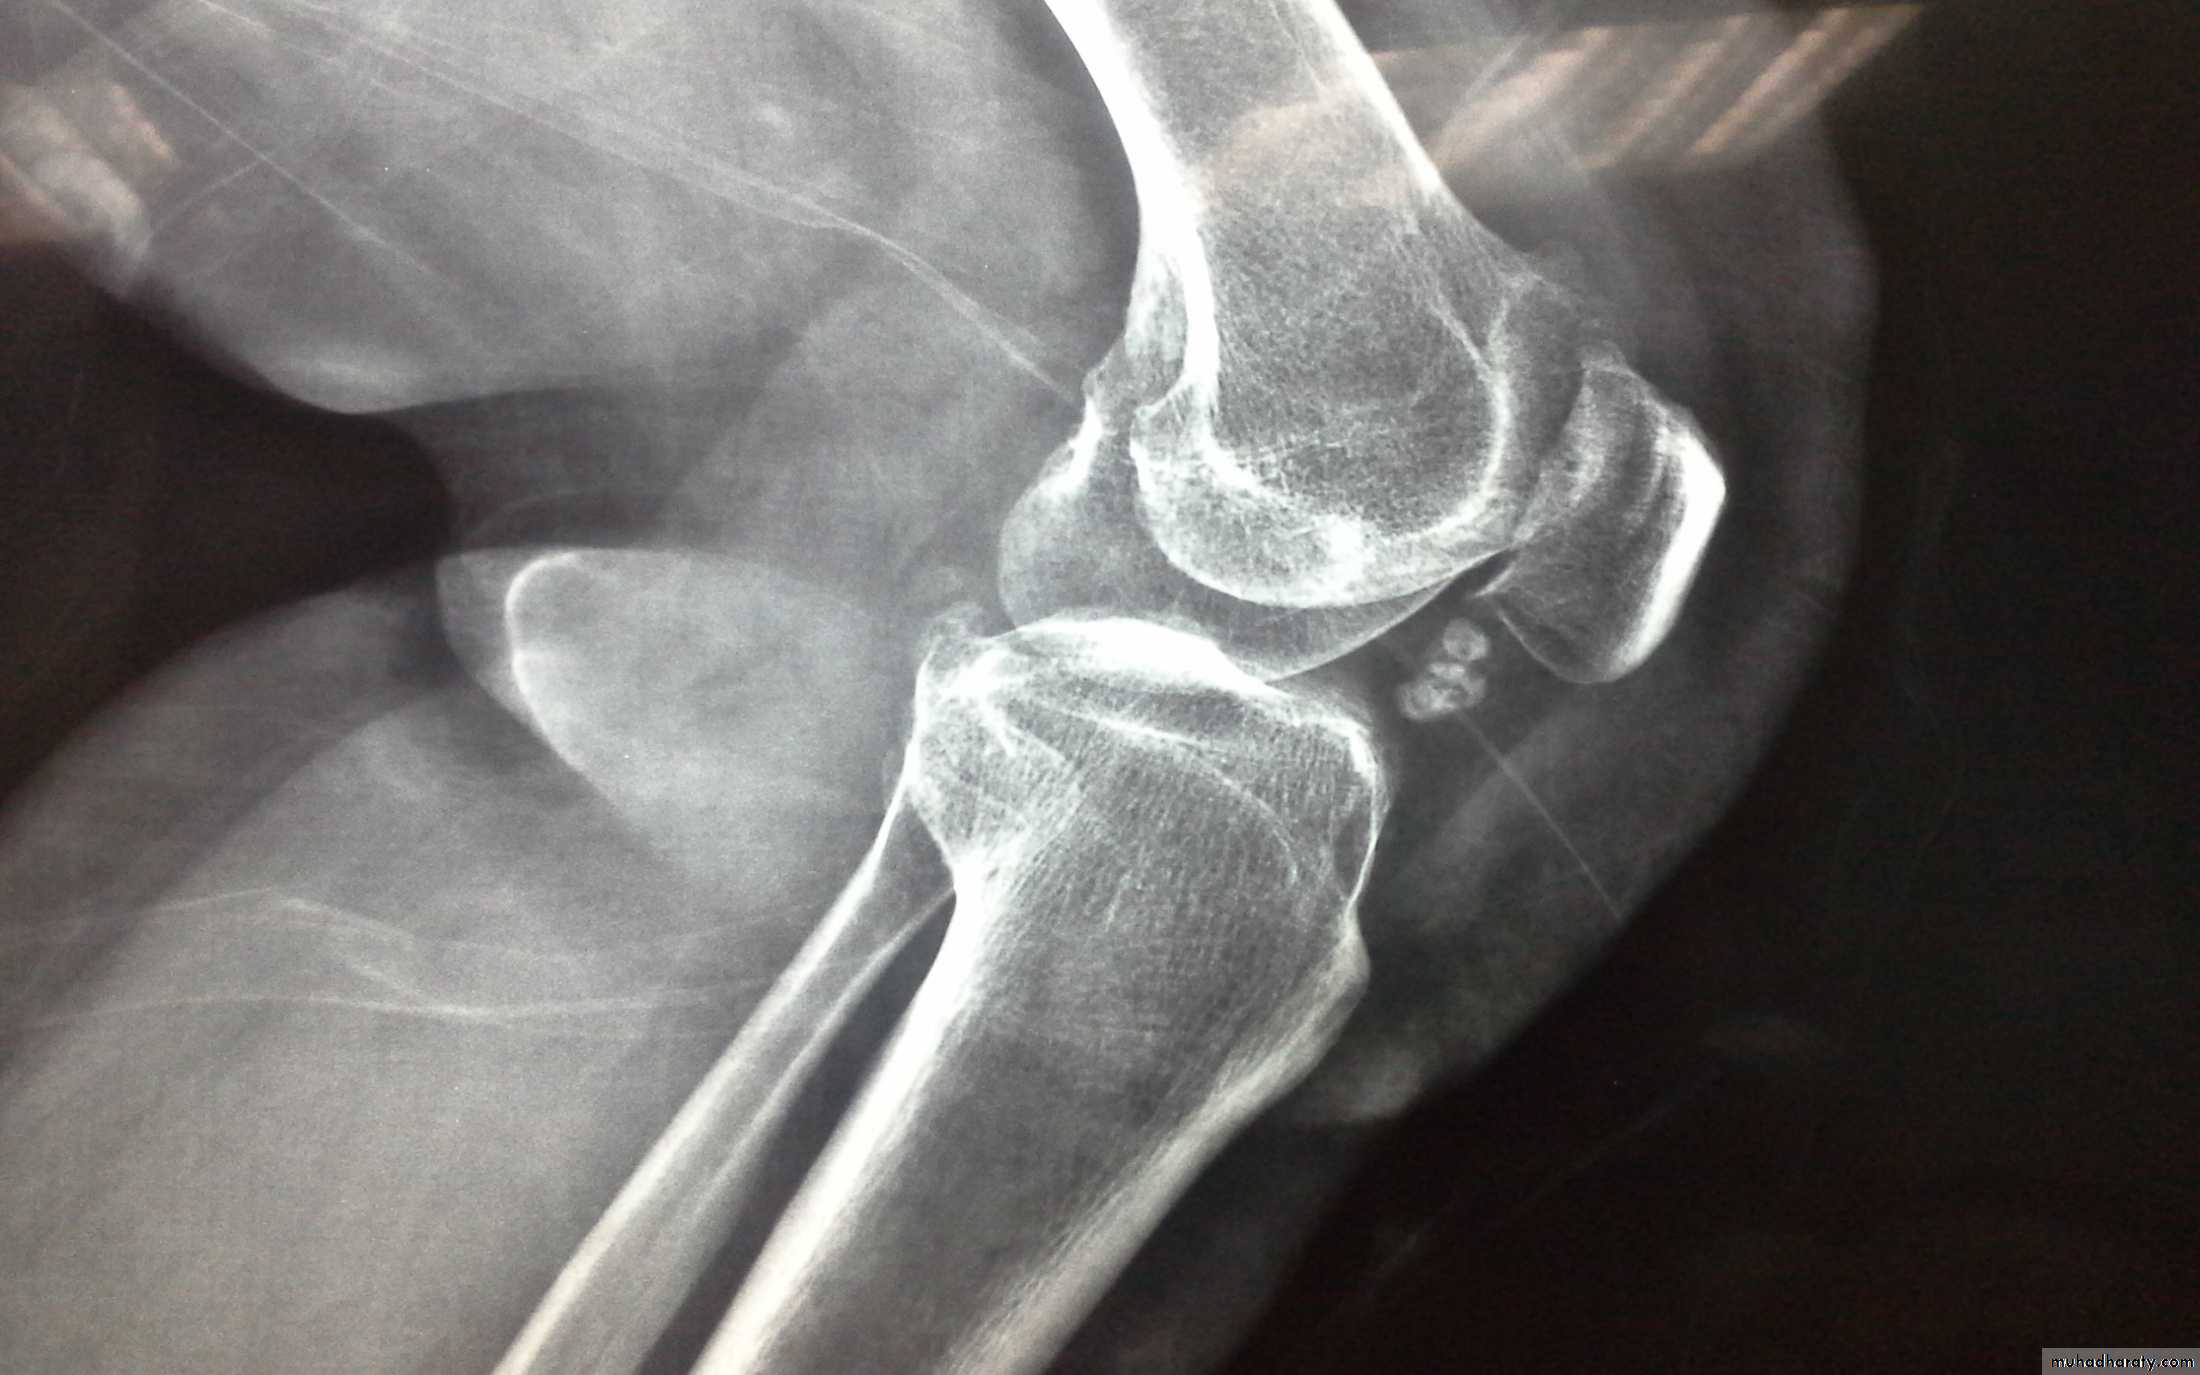

Dx of gout is established by Monosodium urate crystals viewed under the polarizing microscope. X-ray demonstrating typical gouty erosions at the first MTP joint, with well-demarcated erosions, away from the joint line, some with overhanging edges, and adjacent hazy tophaceous material.

-Radiograghs which is :

a-Normal in early stage

b-Later :joint space narrowing ,sclerosis,cyst, osteophyte and gouty erosions( para articular punched out defects)